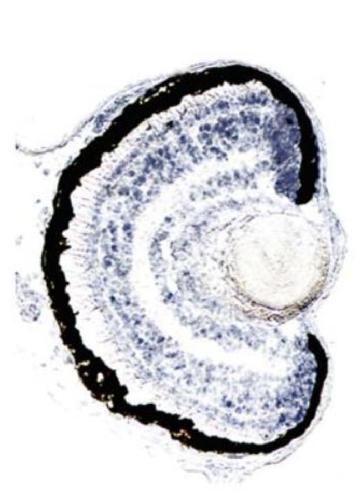

htr2b

5-hydroxytryptamine (serotonin) receptor 2B, G protein-coupled

htr2b encodes a G protein‑coupled receptor that functions as a serotonin‑activated signaling molecule, mediating phospholipase C activation and intracellular calcium release; the protein localizes to t...[+]